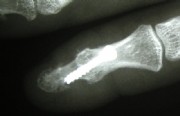

Joint replacement in the wrist area

Left: Severe osteoarthritis (abrasion, joint destruction) of the thumb-saddle joint

Middle: Replacement with a hemiarthroplasty pyrocarbon

Right: This patient had, in addition to the thumb-saddle joint osteoarthritis also signs of wear and instability between the wrist bones. She had severe pain and could not use her hand. We reinforced the pyrocarbon endoprosthesis by stiffening three wrist joints. The patient has been symptom-free for over 10 years now and can use her hand without any restrictions.